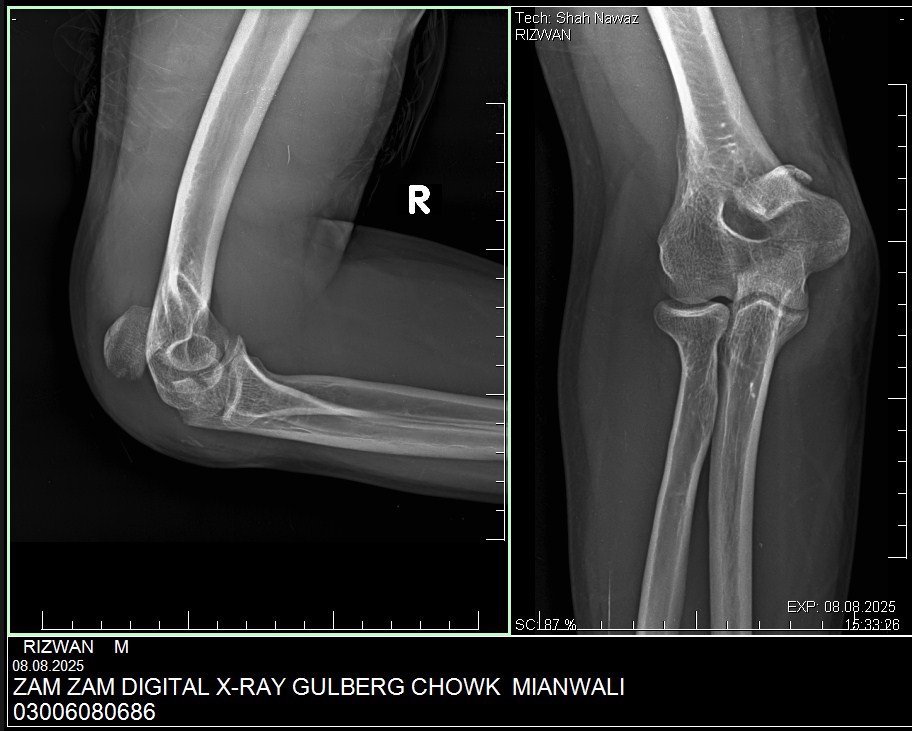

My husband had elbow surgery on 9th of August. I want to know about physiotherapy. When can we start physiotherapy so he can bend and extend his arm freely.Kindly guide us. If we start now will it effect joint or not. TIA

Attach Photo here: